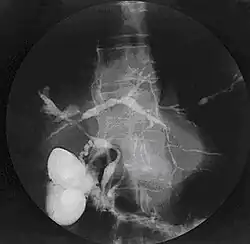

Historically, a cholangiogram would be obtained via endoscopic retrograde cholangiopancreatography (ERCP), which typically reveals "beading" (alternating strictures and dilation) of the bile ducts inside and/or outside the liver. Currently, the preferred option for diagnostic cholangiography, given its noninvasive yet highly accurate nature, is magnetic resonance cholangiopancreatography (MRCP), a magnetic resonance imaging technique. MRCP has unique strengths, including high spatial resolution, and can even be used to visualize the biliary tract of small animal models of PSC.[22]